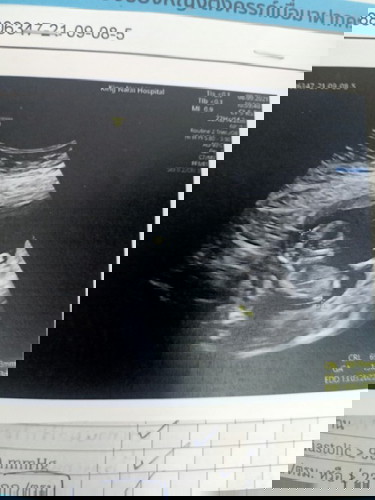

32วีคลูกยังไม่กลับหัว

32วีคแล้วน้องยังไม่กลับมีแม่ๆๆบ้านไหนเป็นเหมือนกันบ้างแล้วมีวิธีแนะนำให้ลูกกลับหัวไหมค่ะ#ขอคำแนะนำหน่อยค่ะ